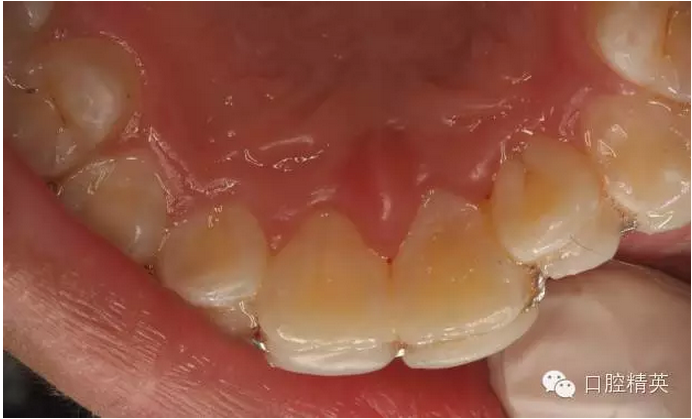

圖4.脫落的21離體牙,根面污染嚴(yán)重

專(zhuān)科檢查:21離體、根面污穢,牙槽窩血凝塊形成穩(wěn)定。